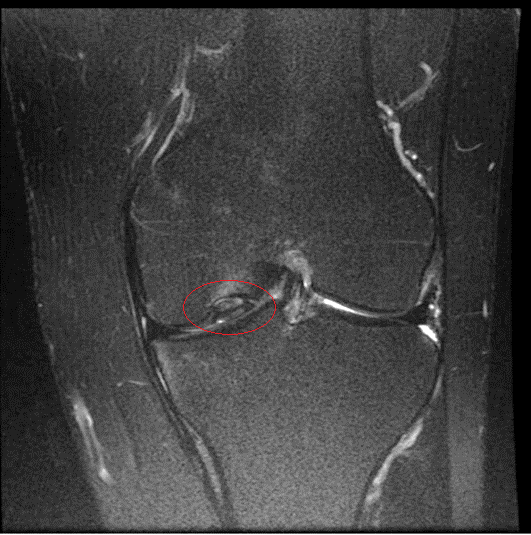

Bei Verdacht auf eine Meniskusverletzung kann eine Magnetresonanztomographie (MRT) Klarheit schaffen. Dabei wird das  Weichteilgewebe des Knies, also die Bänder, Menisken und Muskeln, hochauflösend dargestellt. Anhand der Aufnahmen kann der behandelnde Arzt beurteilen, ob beziehungsweise welcher Teil des Meniskus Schmerzen verursacht.

intakter vs. gerissener Meniskus